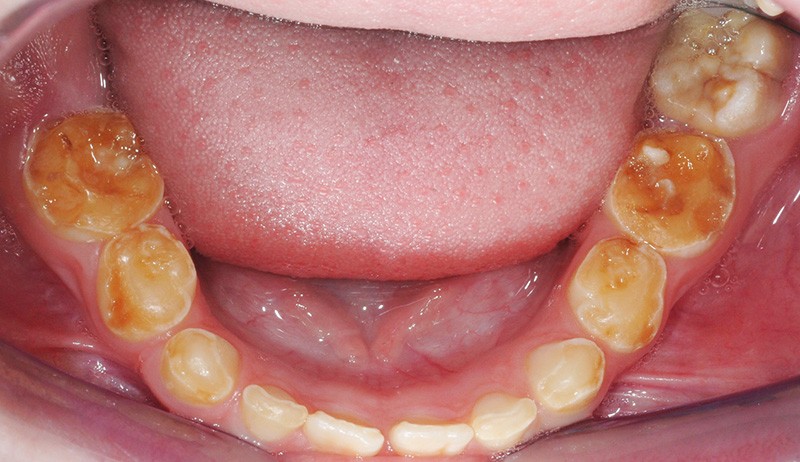

(fig. 2 et 3)

Il s’agit de l’amélogénèse imparfaite héréditaire, qui :

• touche toutes les dents de l’arcade ;

• entraîne une coloration jaune orangée de l’émail sur toute la surface coronaire ;

• est liée à une étiologie génétique.